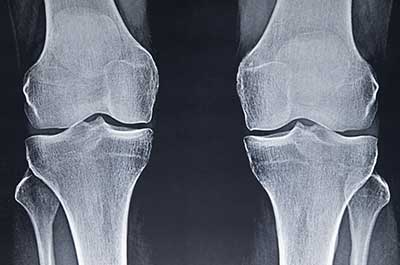

With a total hip replacement, prosthetics are used to replace the entire hip joint: the ball, socket and femoral neck (or part of the thigh bone just below the ball). With hip resurfacing, a prosthetic only replaces the hip socket. It’s called “resurfacing” because the ball is then shaped to fit into the prosthetic hip socket.

Hip resurfacing also differs from a partial hip replacement: With a partial hip replacement, the ball of the hip joint is replaced (along with a bit of the femoral neck) but not the socket.